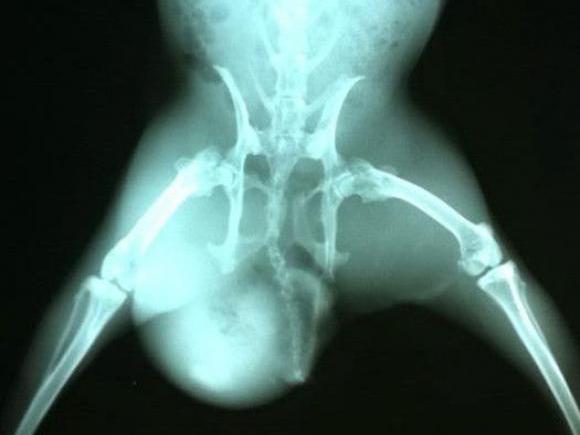

X线检:肾脏膀胱结石